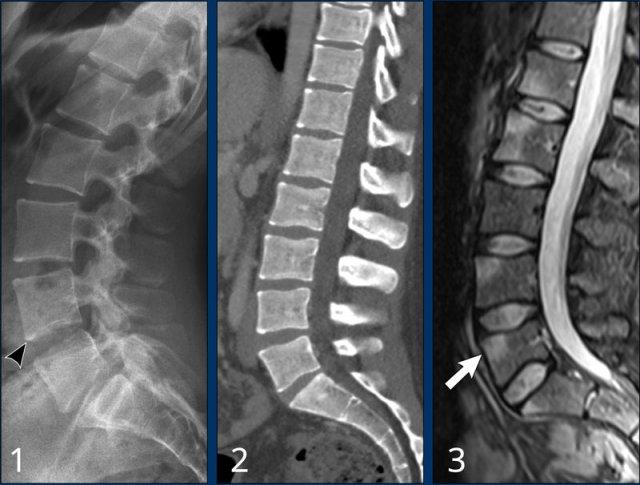

Hình ảnh

Ba bệnh nhân khác nhau với các đặc điểm điển hình của viêm cột sống dính khớp giai đoạn sớm:

- Góc sáng ở bờ trước thân đốt sống, nơi có điểm bám gân. Quan sát thấy hình vuông hóa thân đốt sống.

- Bệnh nhân khác với hình vuông hóa và góc sáng thân đốt sống trên CT.

- Bệnh nhân này có phù nề tại điểm bám gân của thân đốt sống, quan sát được trên chuỗi xung STIR mặt phẳng sagittal.